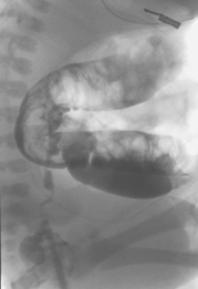

Nel gruppo A sono stati eseguiti in tutti i casi CO e BRS, per un totale di 42 campioni rettali (3 per ogni paziente). Non è stata registrata alcuna complicanza a breve e lungo termine. Il CO ha mostrato in due casi (14%) dilatazione del colon con cono di transizione, segni suggestivi di MH (Fig. 8), dilatazione del colon in 6 casi (43%), mentre reperto normale era presente nei restanti 6 casi.

Figura 8. Immagine radiologica:

tratto agangliare (frecce) e tratto dilatato (asterisco)